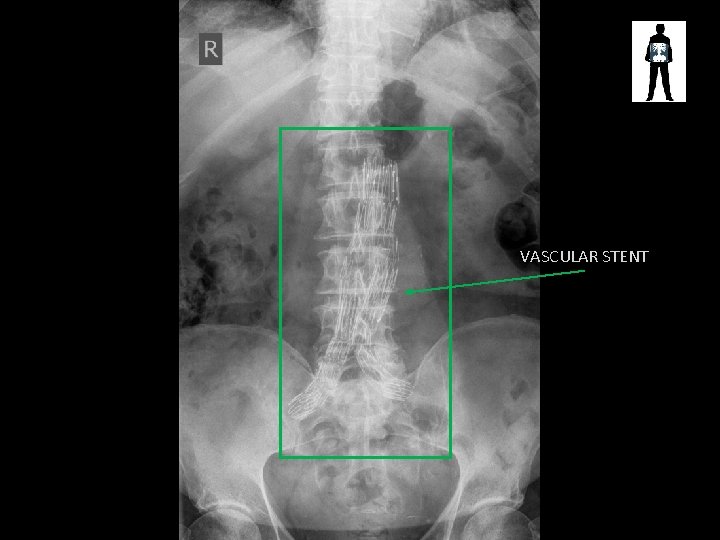

VASCULAR STENT

Aortic Stent • Used to treat aneurysm • Deployed when aneurysms are not near arteries that could be occluded (renal, etc)